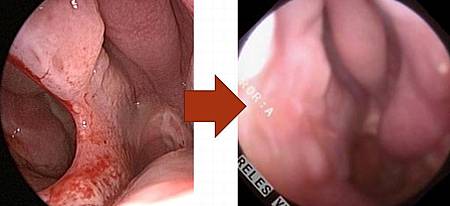

1. 測量:可先用尺和內視鏡確立大小與範圍,方便與病患溝通。

3. 手術方式(小洞): 如破損較小,可使用局部擴張或轉位(local flap),在內視鏡下以鼻中隔黏膜皮瓣或下鼻甲皮瓣修補。

4. 手術方式(大洞): 若破損較大,可考慮開放式鼻整形(Open rhinoplasty)修補,使用鼻道下方黏膜。

此方式為目前成功率最高的修補方式,也是最常使用的手術法。